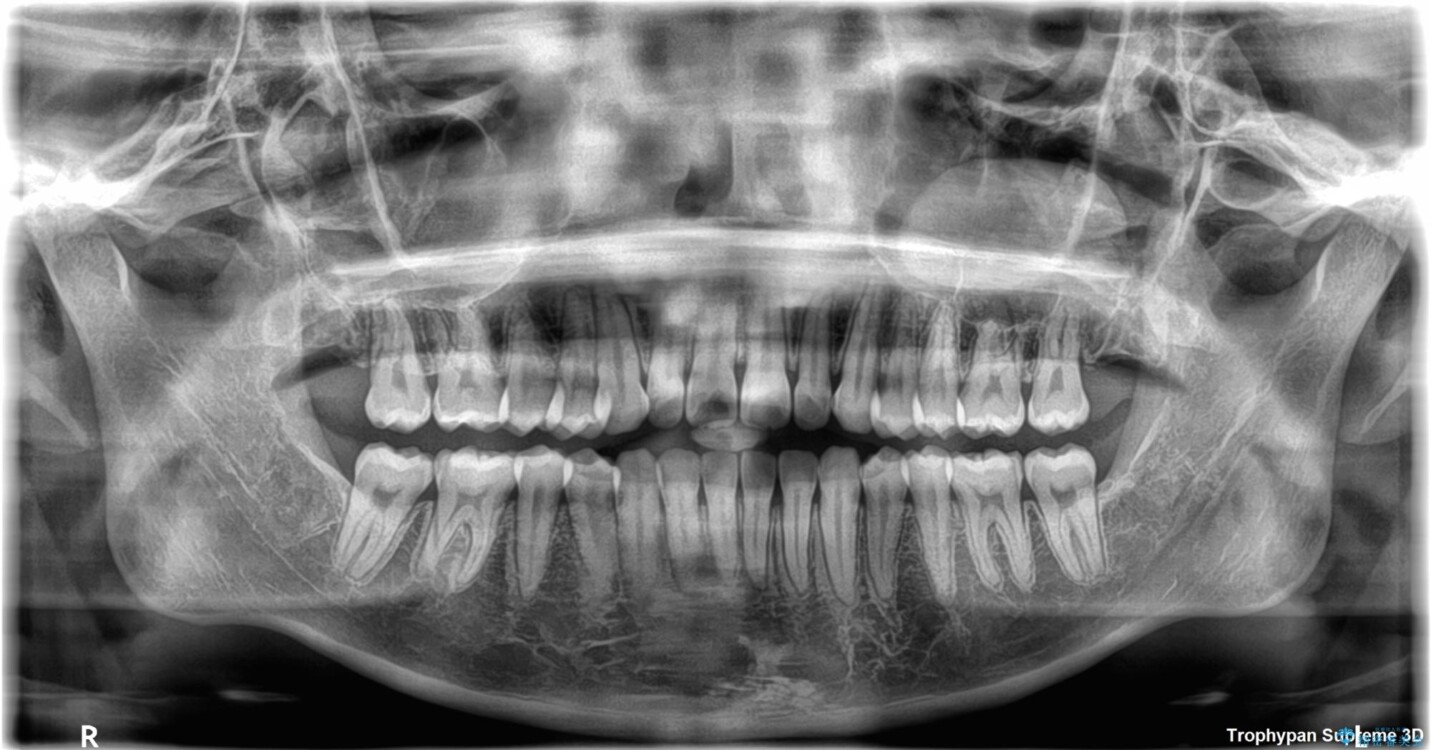

前歯のデコボコが気になるでのことで来院された患者様です。

歯列アーチが狭くスペース不足により前歯がデコボコしている状態でした。見た目を改善しつつ、前歯を前方に突出させず、自然な笑顔を目指したいというご希望でした。

・アーチを側方に拡大して歯が並ぶスペースを確保

・抜歯は避け、非抜歯での対応

・目立ちにくい審美装置による矯正

・治療期間をできるだけ短縮するために、綿密な装置管理と協力体制を構築